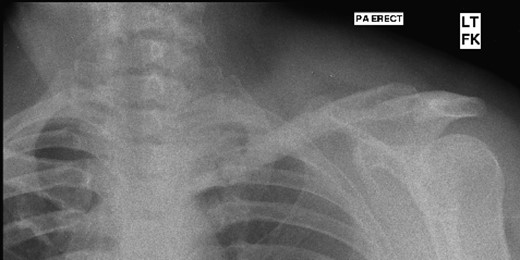

The patient had 3 monthly follow-up and at 2 years, there was no evidence of local recurrence or complications. She had a full and pain-free range of motion of the shoulder and was completely asymptomatic (Fig. 4).